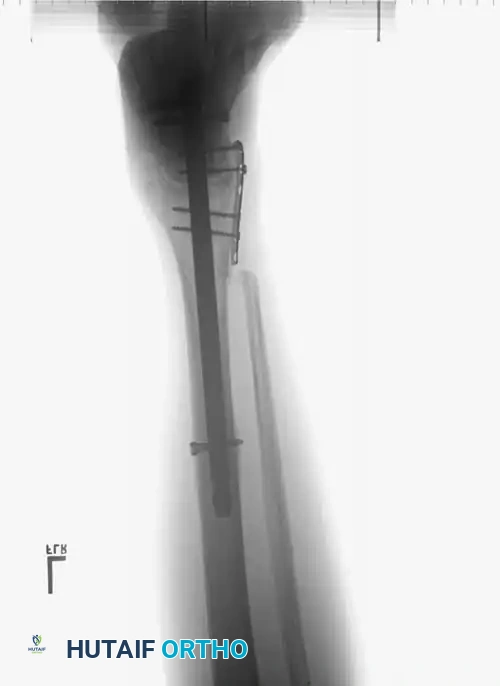

In cases of severe medial comminution, a mini-fragment plate (e.g., 2.0 mm or 2.4 mm) may be applied to the medial talar neck to act as a buttress and maintain length, preventing varus collapse.

Post-op fixation 3